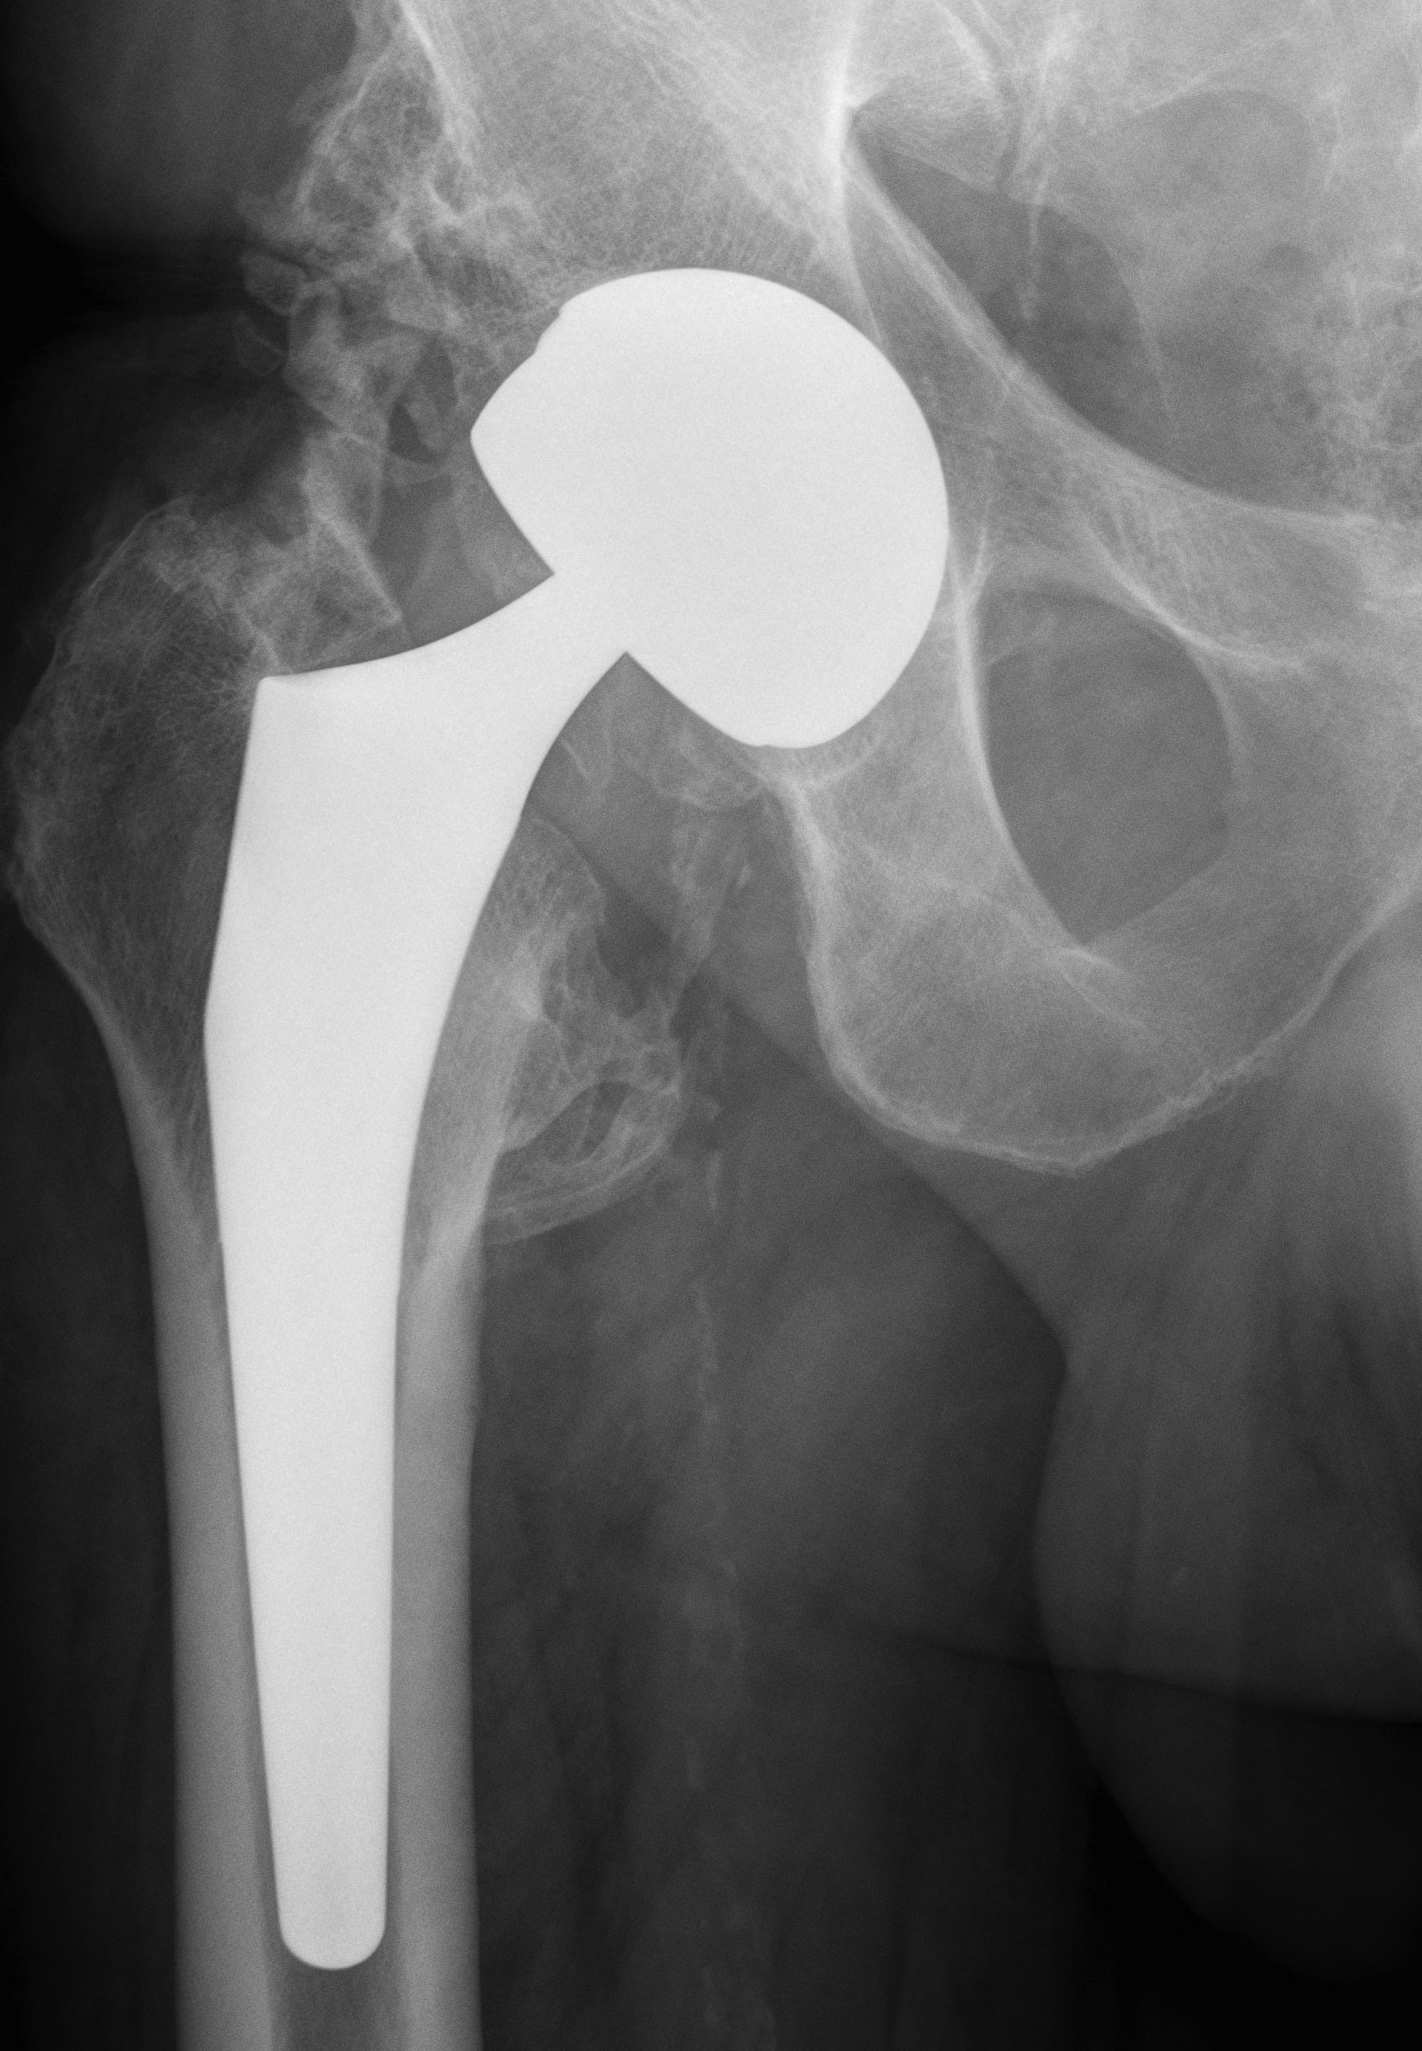

Dual mobility

Stryker dual mobility

Concept

Stryker dual mobility

Wear

Stability

Normal feel of hip

Increased ROM

Large head

- increase volumetric wear

- less penetrative / linear wear

Small head

- increased linear wear

- decreased volumetric wear